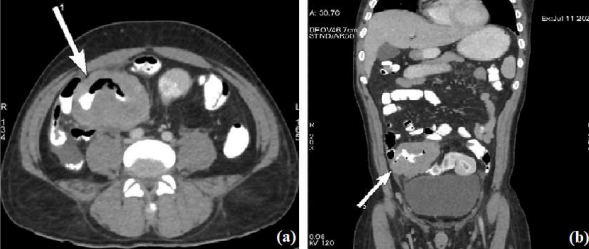

Post-surgery histopathology report was suggestive of non-Hodgkin’s lymphoma. Microscopic examination showed large atypical lymphoid cells with scant cytoplasm and vesicular nuclei with distant nucleoli, classical of diffuse large B cell lymphoma (DLBCL) (Fig. 3). Immunohistochemistry (IHC) was done to confirm and further type and grade the lymphoma. IHC findings were diffuse reactivity for CD20 (pan B cell antigen) with high Ki67 proliferation index of 95% (Fig. 4a and b); also dim nuclear reactivity for transcription factor Multiple Myeloma 1(MUM1), suggestive of DLBCL non-germinal centre type (Fig. 4c).

Fig. 3. High power histopatological images showing monotonous infiltrate of large atypical lymphoid cells with scant cytoplasm and vesicular nuclei suggestive DLBCL.

Fig. 4a. IHC images showing diffuse reactivity for CD20 with (b) high Ki67 proliferation index of 95%. (c) Also dim nuclear reactivity for transcription factor MUM1, suggestive of DLBCL non-germinal centre type.